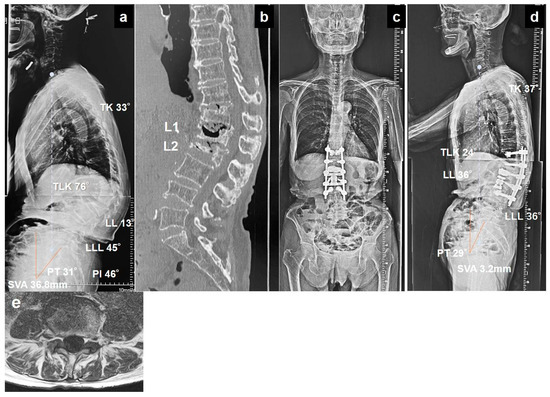

25 February 2026

Background: Kyphotic deformity following osteoporotic vertebral fracture (KDOVF) often requires corrective surgery to restore sagittal alignment; however, mechanical complications, such as proximal junctional failure (PJF) and distal junctional failu...